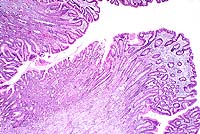

Case 5-3. Stomach. Note mucosal hyperplasia with giant folds. 2X

AFIP Diagnosis: Stomach: Hyperplasia, mucosal, diffuse, marked, with mild lymphoplasmacytic and eosinophilic gastritis, baboon (Papio cynocephalus), primate.

Conference Note: The Division of Gastrointestinal Pathology of the AFIP also reviewed this case and agreed that the giant folds are consistent with Menetrier's disease (MD).

In humans, MD is a gastric giant folds disease syndrome, but all parts of the syndrome may not be present at the same time. The full syndrome includes giant folds, gastric protein loss, and decreased gastric acid production, accompanied by a histologic complex that includes foveolar hyperplasia and distortion, glandular atrophy, and edema but little inflammation, in the lamina propria.5 The gastric pits (foveolae) are unusually elongated, and frequently extend from the surface to the base of the mucosa. They occasionally penetrate the muscularis mucosa, ending as cysts surrounded by smooth muscle. The superficial lamina propria is usually edematous, and may contain low numbers of plasma cells and eosinophils.

The cause of MD is unknown; however, it is now being linked to excessive levels of growth factors, particularly transforming growth factor alpha (TGFa). A histologically and clinically identical condition has been produced in transgenic mice that overexpressed TGFa in their stomachs.5